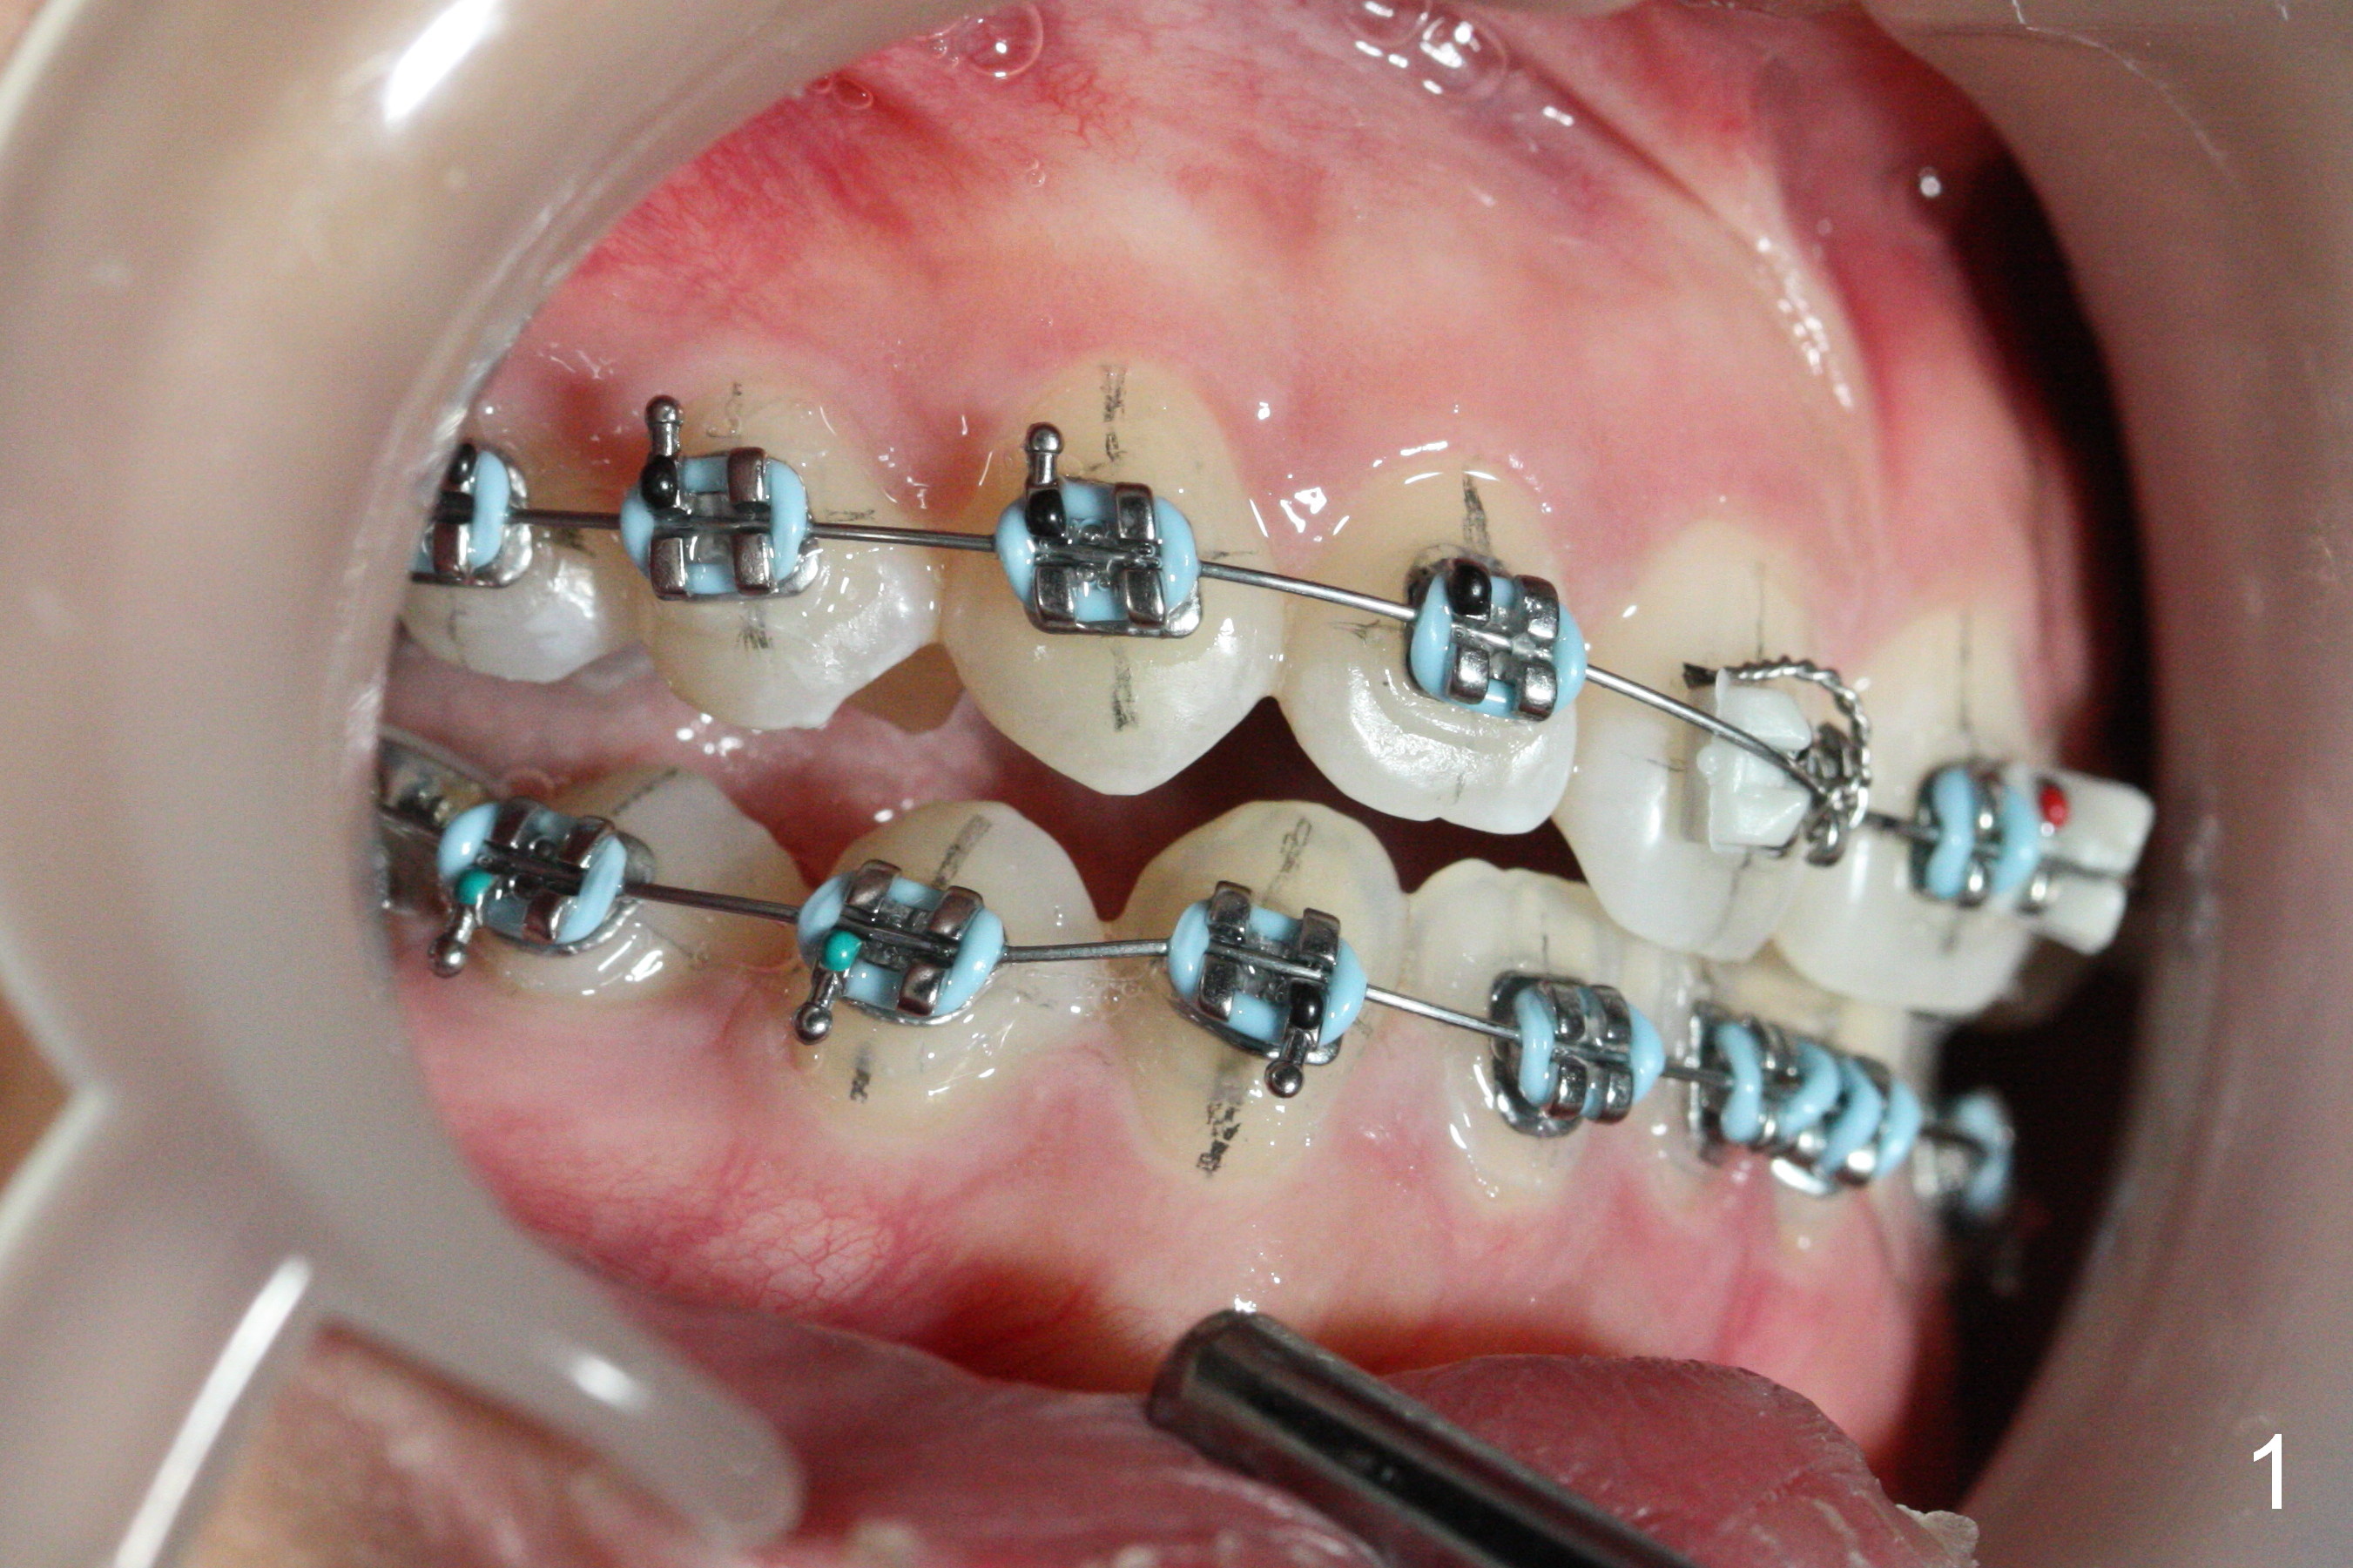

Class II Division II malocclusion is characterized by the lingual inclination of the upper anterior teeth so that there is not enough clearance to place brackets for the lower incisors (Fig.1). Composite has to be placed on the occlusal surface of the molars (Fig.3 *). The patient must have difficulty in mastication for a few days. Is there a better method to avoid the inconvenience?